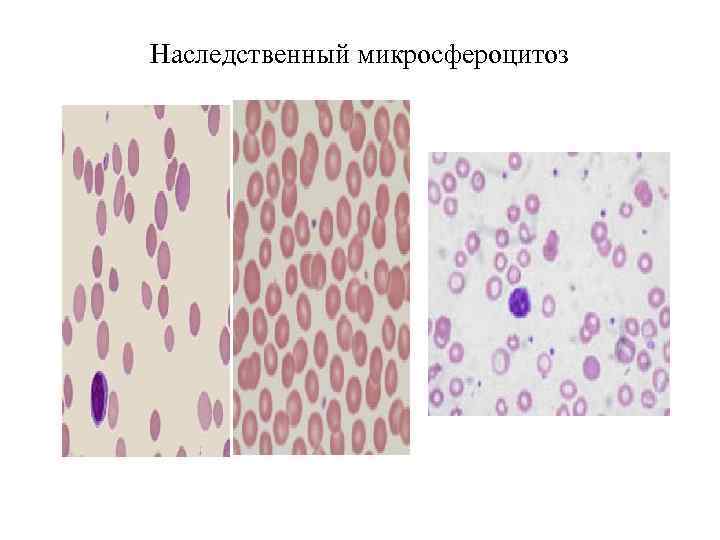

Гемограмма при гемолитической анемии • 1. Серповидноклеточная анемия, талассемия • 2. Наследственный микросфероцитоз • 3. 4. 5 Аутоиммунные

Гемолитические анемии Анемии вследствие усиленного кроверазрушения (гемолитические): - наследственные: 1) связанные с нарушением структуры мембраны эритроцитов (микросфероцитоарная анемия Миньковского – Шаффара, овалоцитоз, акантоцитоз), 2) связанные с дефицитом ферментов в эритроцитах, 3) связанные с нарушением синтеза гемоглобина (серповидноклеточная анемия, гемоглобинозы, талассемия) - приобретенные: 1) аутоиммунные, 2) пароксизмальная ночная гемоглобинурия, 3) лекарственные, 4) травматические и микроангиоспастические, 5) вследствие отравления гемолитическими ядами и бактериальными токсинами. - анемии смешанные

Гемолитические анемии делятся на иммунные и неиммунные. К неиммунным гемолитическим анемиям относятся: 1. Врожденные. - мембранопатии (наследственный микросфероцитоз, овалоцитоз, стоматоцитоз, эллиптоцитоз, пиропойкилоцитоз). - ферментопатии (дефицит в эритроцитах ферментов Г- 6 ФД и глутатионредуктазы). - гемоглобинопатии (талассемии и различные варианты носительства нестабильного Нb). 2. Приобретенные гемолитические анемии

Наследственный микросфероцитоз